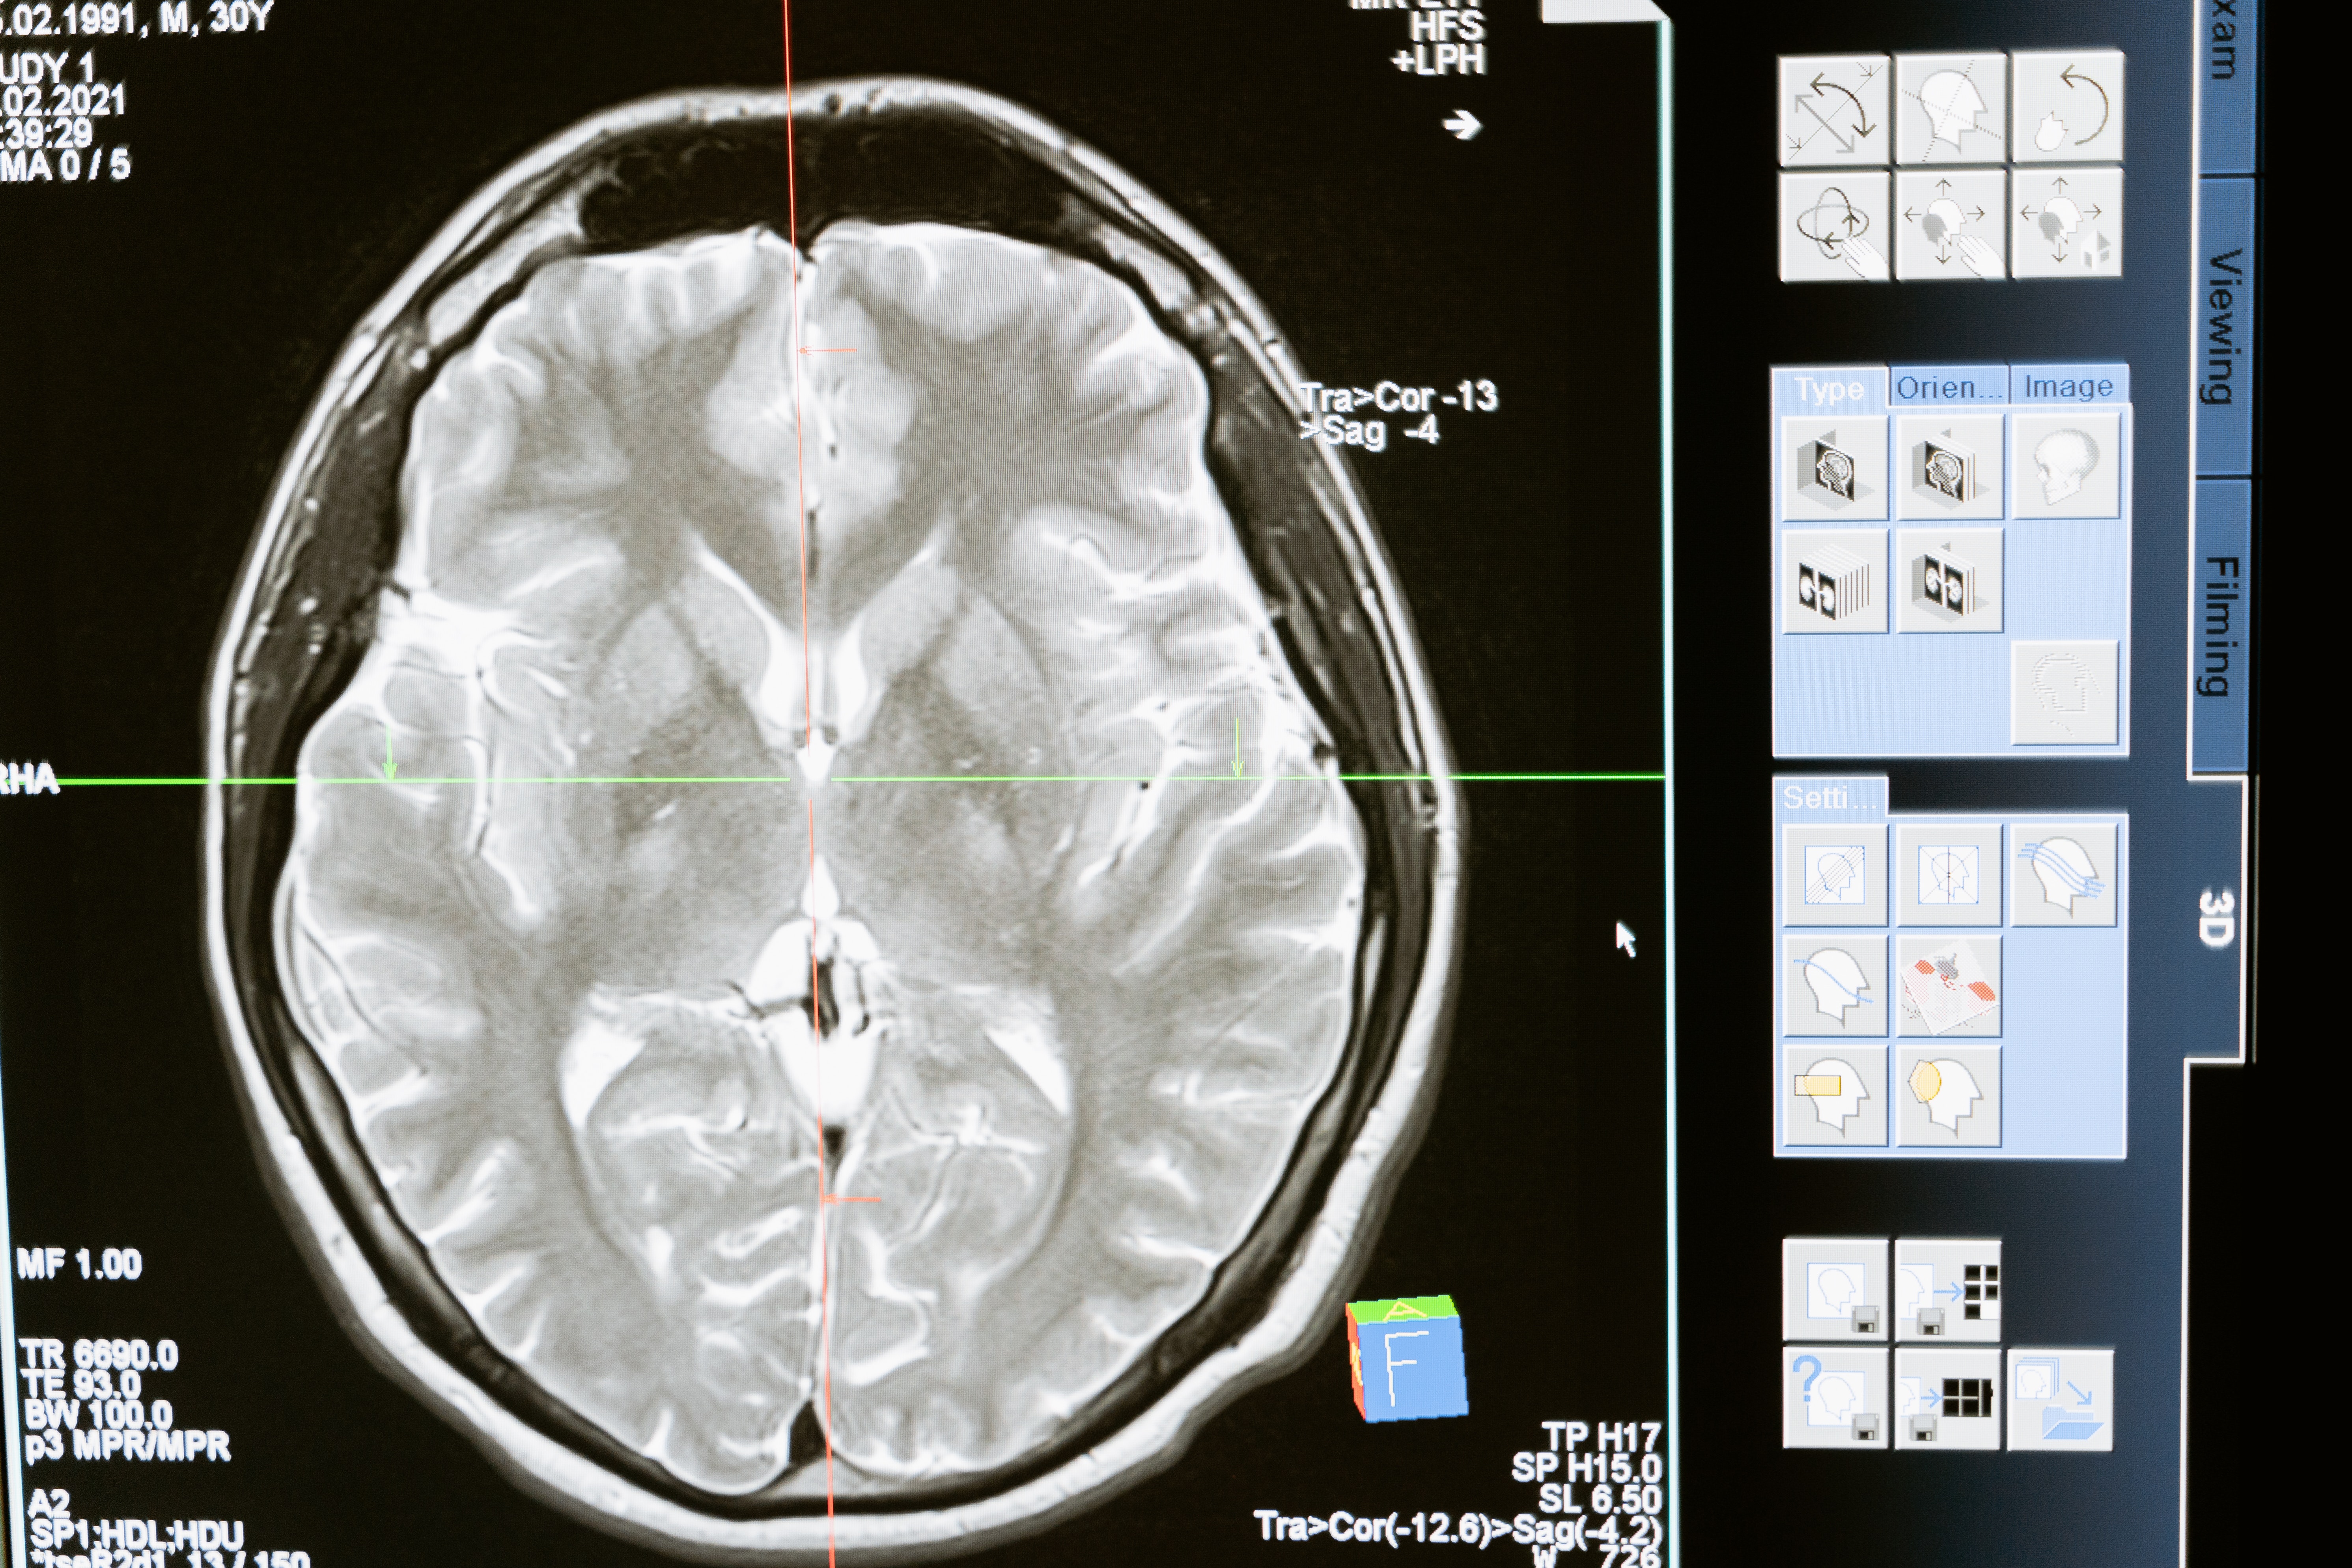

Znanstvenici s Imperial College Londona proveli su testove na miševima koji su imali glioblastom (GBM) - jedan od najagresivnijih oblika raka mozga. Glodavcima su dali eksperimentalni lijek koji im je oduzeo aminokiselinu arginin - vitalnu hranjivu tvar koju tumori koriste za rast.

GBM je najčešći tip primarnog tumora mozga visokog stupnja u odraslih, a ujedno je i najagresivniji i najsmrtonosniji. Manje od jedan posto pacijenata s GBM-om poživi više od deset godina, a za mnoge je prognoza samo 12 mjeseci.